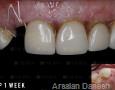

Pictures

1 Weeks